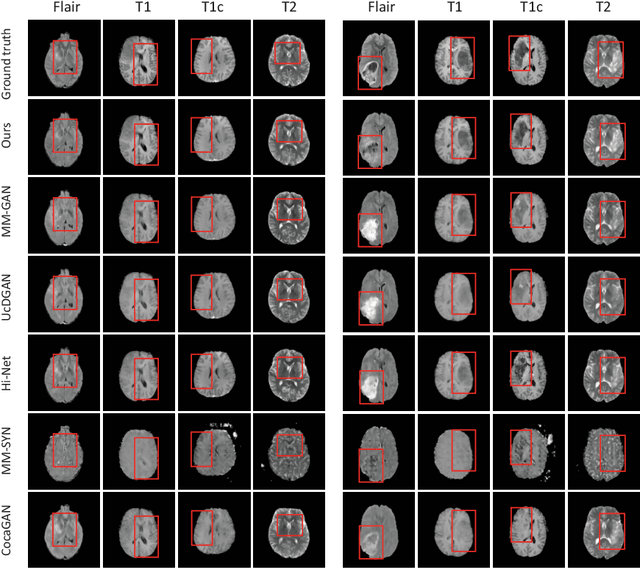

Abstract:Multi-modal medical image completion has been extensively applied to alleviate the missing modality issue in a wealth of multi-modal diagnostic tasks. However, for most existing synthesis methods, their inferences of missing modalities can collapse into a deterministic mapping from the available ones, ignoring the uncertainties inherent in the cross-modal relationships. Here, we propose the Unified Multi-Modal Conditional Score-based Generative Model (UMM-CSGM) to take advantage of Score-based Generative Model (SGM) in modeling and stochastically sampling a target probability distribution, and further extend SGM to cross-modal conditional synthesis for various missing-modality configurations in a unified framework. Specifically, UMM-CSGM employs a novel multi-in multi-out Conditional Score Network (mm-CSN) to learn a comprehensive set of cross-modal conditional distributions via conditional diffusion and reverse generation in the complete modality space. In this way, the generation process can be accurately conditioned by all available information, and can fit all possible configurations of missing modalities in a single network. Experiments on BraTS19 dataset show that the UMM-CSGM can more reliably synthesize the heterogeneous enhancement and irregular area in tumor-induced lesions for any missing modalities.